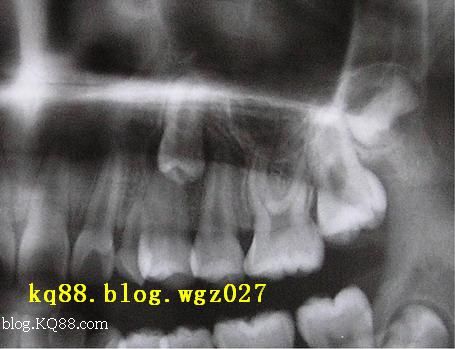

2、牽引導(dǎo)萌矯治法(見(jiàn)附圖1~圖6)

適應(yīng)證:已無(wú)萌出能力的埋伏牙及尚有萌出能力的異位牙。如近遠(yuǎn)中傾斜埋伏的上尖牙,牙體形態(tài)正常。

術(shù)前準(zhǔn)備:常規(guī)矯治,開(kāi)展或維持埋伏牙的有效間隙。拍攝X 線牙片,咬合片及用手指觸診定位,確定開(kāi)窗部位準(zhǔn)備粘接附件,設(shè)定牽引方法。

③對(duì)于一些特殊的埋伏牙,國(guó)外一些學(xué)者采用內(nèi)科螺旋固位釘鉆入切緣釉質(zhì)內(nèi)作為牽引附件的方法,其操作更為簡(jiǎn)單。但操作不慎有可能損傷牙髓。提示:對(duì)于牙體形態(tài)異常、牙根彎曲角度大的埋伏阻生畸形牙,應(yīng)選擇外科手術(shù)拔除。附圖牽引導(dǎo)萌矯治法: